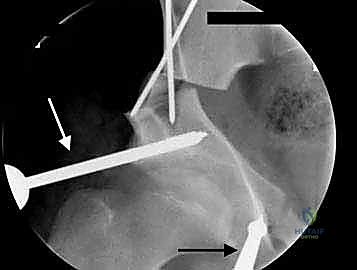

باستخدام أدوات خاصة، يقوم الدكتور هطيف بتدوير التجويف الحقي الحر في ثلاثة أبعاد (للأمام، وللخارج، وللأسفل) حتى يغطي رأس عظم الفخذ بشكل مثالي وميكانيكي سليم. يتم التحقق من الزاوية الجديدة فوراً داخل غرفة العمليات باستخدام جهاز الأشعة السينية المتحرك (C-arm).

5. التثبيت القوي (Fixation)

بمجرد الوصول إلى الوضع المثالي، يتم تثبيت العظام في مكانها الجديد باستخدام براغي معدنية قوية من التيتانيوم أو دبابيس (K-wires). هذا التثبيت يضمن التحام العظام بشكل صحيح خلال فترة التعافي.